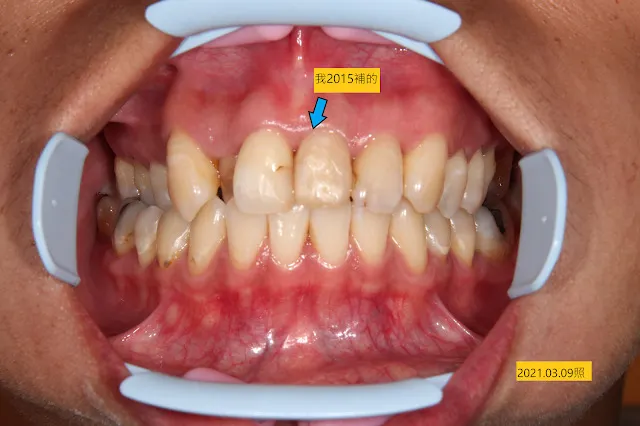

臨床如下圖,我不是要故意炫耀我補的多好...其他有斑點的,再次蛀牙的,全都是在別家補的....而只是要指出一個事實,很多人聽不懂我說口腔是一個潮濕的環境,其臨床意義是什麼?收邊沒收好,加上時間的複利,您知道您的牙科緣為何斬不斷了吧?),而造成N次蛀牙。這次挖開都已到要抽神經的懸崖邊緣了,下次再蛀,直接痛起來,要做根管治療抽神經的機率大增。

之前的補牙微滲漏染色,左上正中門牙才是我補的(箭頭所指),其他的,不是